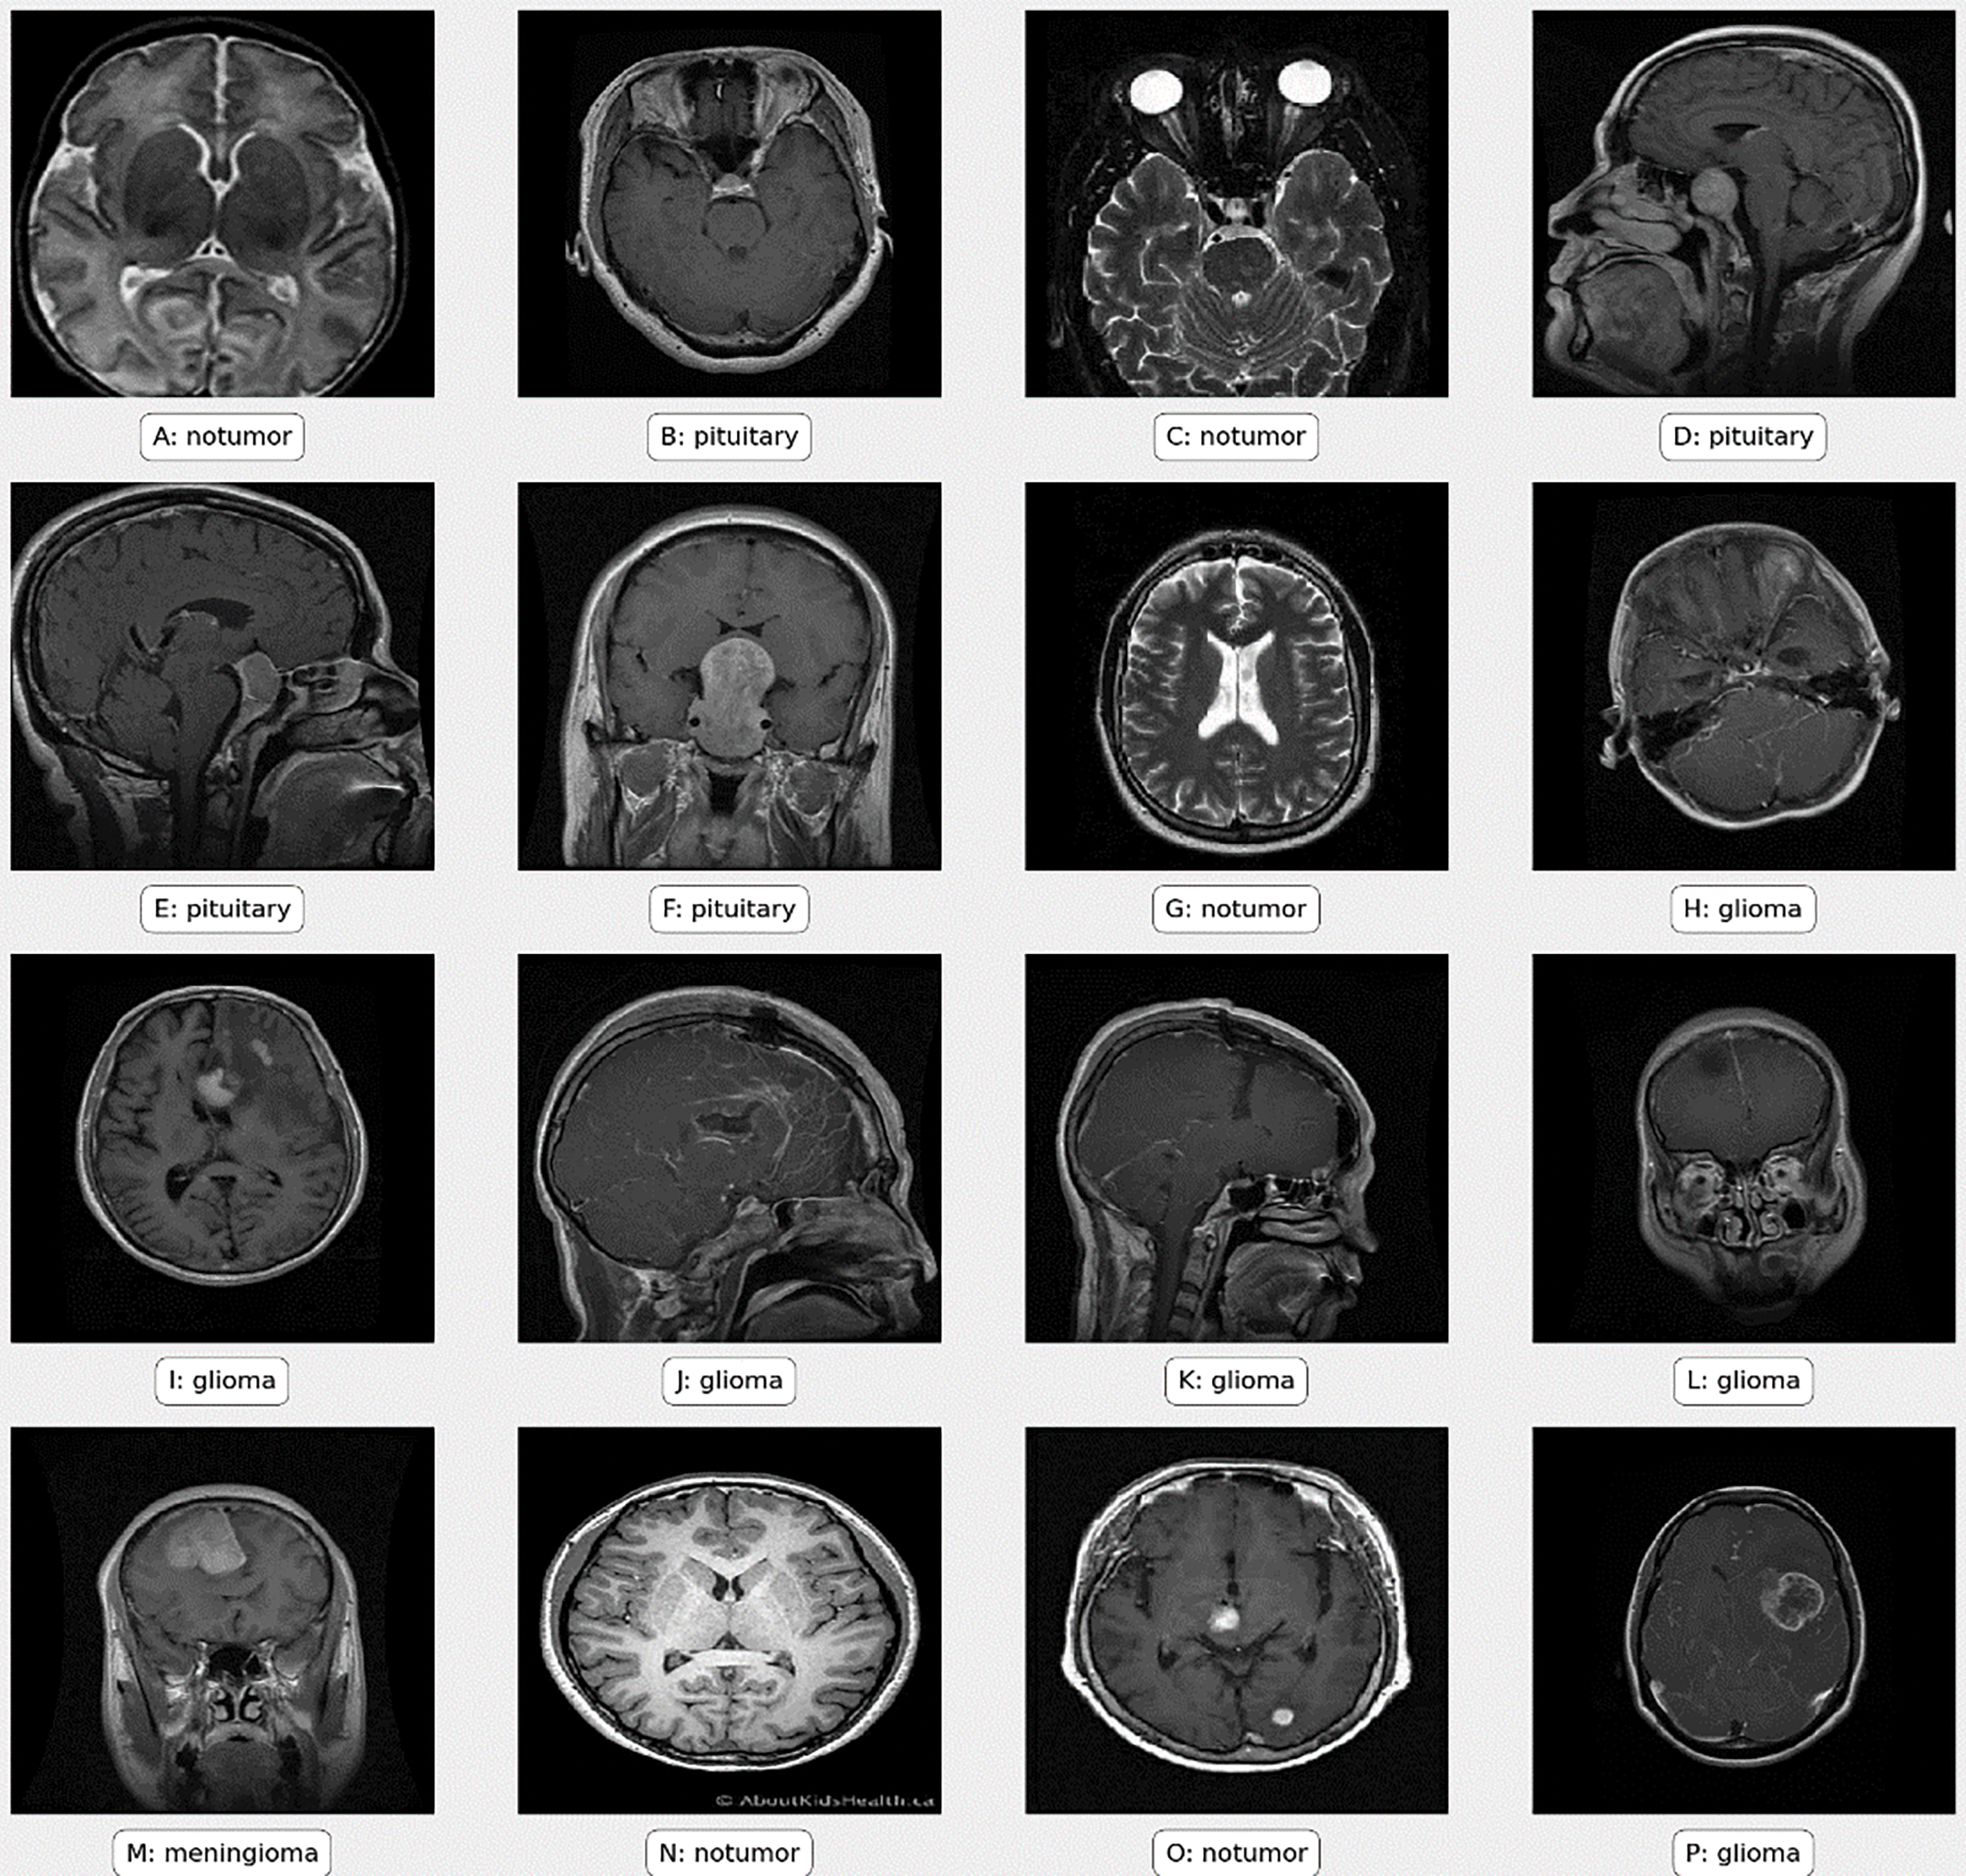

Preprocessing is crucial in machine learning, especially for handling medical images such as MRI scans used in brain tumor classification. Fig. 2 illustrates sample images from the dataset, processed using Eq. (1).

Figure 2: Sample images from the dataset